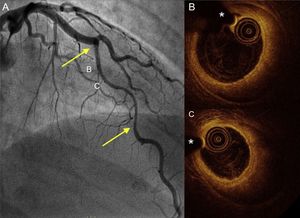

The therapeutic management of patients with SCAD is summarized in Table 3. Percutaneous coronary intervention was performed in half of the patients; 64% (n = 23) of these patients received a drug-eluting stent. Percutaneous coronary intervention was used primarily for patients diagnosed more than 10 years earlier, and conservative medical management was more frequent in more recently diagnosed patients (27% were conservatively managed before 2011 vs 61% after; P = .008). Only 1 patient who had a concomitant aortic dissection required coronary artery bypass surgery. Notably, a more conservative medical treatment strategy was chosen (79% [n = 15] vs 41% [n = 22]; P = .007) in the SCAD group with hypothyroidism (with a more distal and diffuse involvement and somewhat smaller and more tortuous vessels). Illustrative examples from this series are shown in Figure 1 and Figure 2.

Coronary angiography and OCT imaging in a hypothyroid patient with spontaneous coronary artery dissection. A: angiogram of the anterior descending artery with a large type 2 dissection (arrows). B and C: OCT images of the proximal and mid segments showing a complete intimomedial flap separating the false lumen (large intramural hematoma) from the real one, where the OCT catheter and guidewire are located. OCT, optical coherence tomography. *Wire artifact.